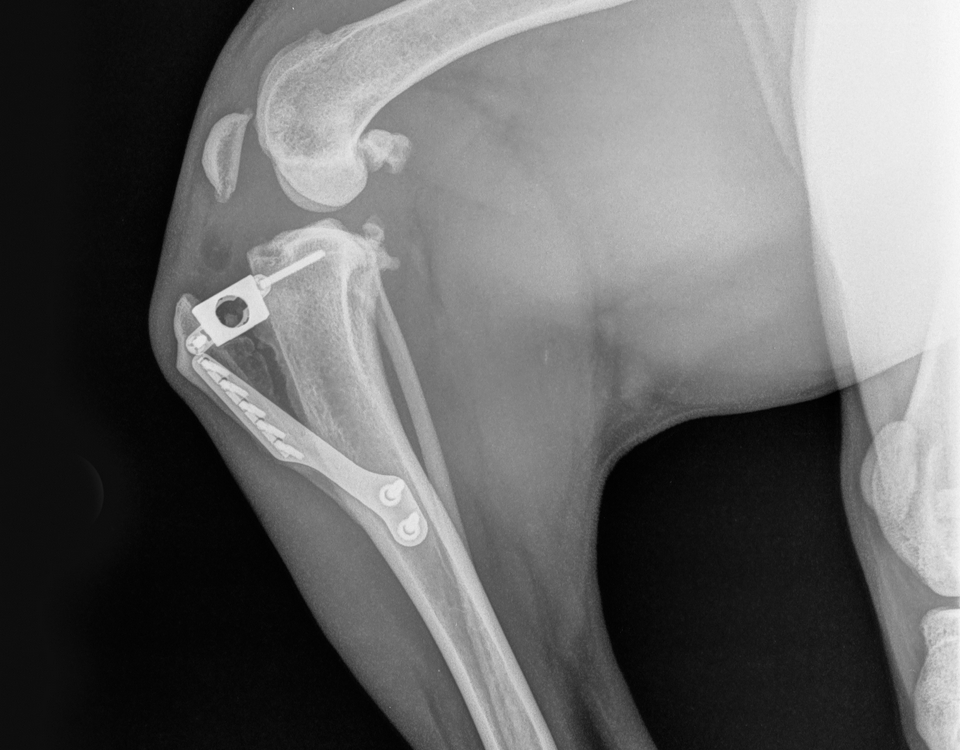

Nous réalisons notamment la réduction et la stabilisation des fractures, les ligamentoplasties extra-articulaires, ainsi que des techniques spécialisées telles que la TPLO (ostéotomie de nivellement du plateau tibial) pour les ruptures du ligament croisé.

En fonction des cas, nous pratiquons également l’arthrodèse partielle ou totale, les greffes osseuses ou la résection de la tête et du col fémoral. Pour les luxations de hanche, la méthode TightRope permet une stabilisation efficace et mini-invasive.